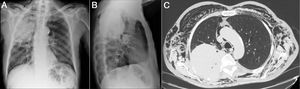

(A and B) Plain chest X-ray in PA and lateral projections. Voluminous mass in right upper lobe, and minor cervical subcutaneous emphysema. (C) Chest CT (axial slice, mediastinum window). Resorption of posterior costal arches at the site of the mass, pneumomediastinum and massive subcutaneous emphysema.

We report the case of a 69-year-old man, former smoker, who attended the emergency department with constitutional symptoms and pain in the right shoulder. Chest radiograph (Fig. 1A and B) revealed a mass in the right upper lobe. His symptoms were controlled and he was referred to the respiratory medicine department, where positron emission tomography and chest computed tomography (CT) were performed, showing destruction of the ribs by the mass with incipient signs of subcutaneous emphysema. A few days after the biopsy (epidermoid carcinoma), he presented in our hospital with significant clinical deterioration. Examination revealed cervicofacial swelling, thoracocervical crackles, and hypophonesis in right fields, with tachypnea and arterial oxygen saturation of 93%. Urgent CT was performed (Fig. 1C), showing pneumomediastinum and massive subcutaneous emphysema. The patient was admitted to the oncology department, where 2 subcutaneous Penrose® drainage tubes were inserted, producing clinical and radiological improvement.